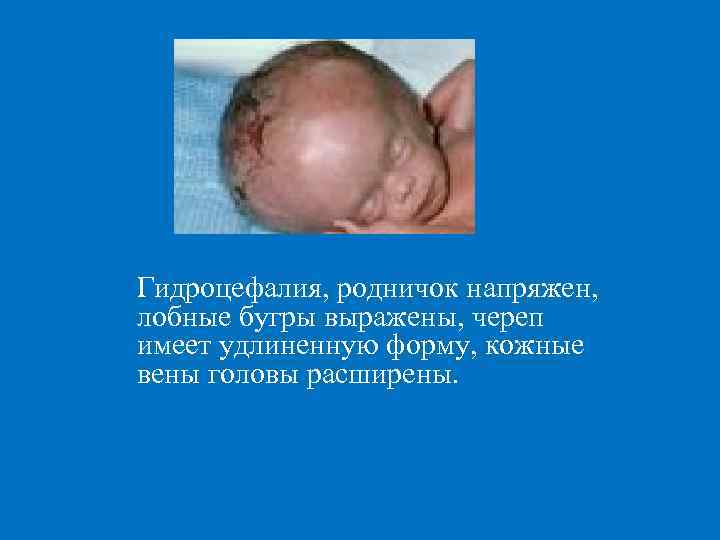

ДИФФУЗНАЯ ПАПУЛЁЗНАЯ ИНФИЛЬТРАЦИЯ § Локализация – ладони и подошвы, лицо, ягодицы, задняя поверхность бедер и голеней. § Кожа ладоней и подошв инфильтрируется, складки сглаживаются. § Цвет синюшно-красный, поверхность блестящая, «лакированная» , теряется эластичность, появляются трещины ( «рука прачки» ). § Процесс заканчивается крупнопластинчатым шелушением. § Инфильтрация Гохзингера: за счет растяжения при крике, сосании, на коже и слизистой оболочке вокруг рта образуются глубокие радиальные трещины после заживления которых образуются «лучистые рубцы» Робинсона– Фурнье.